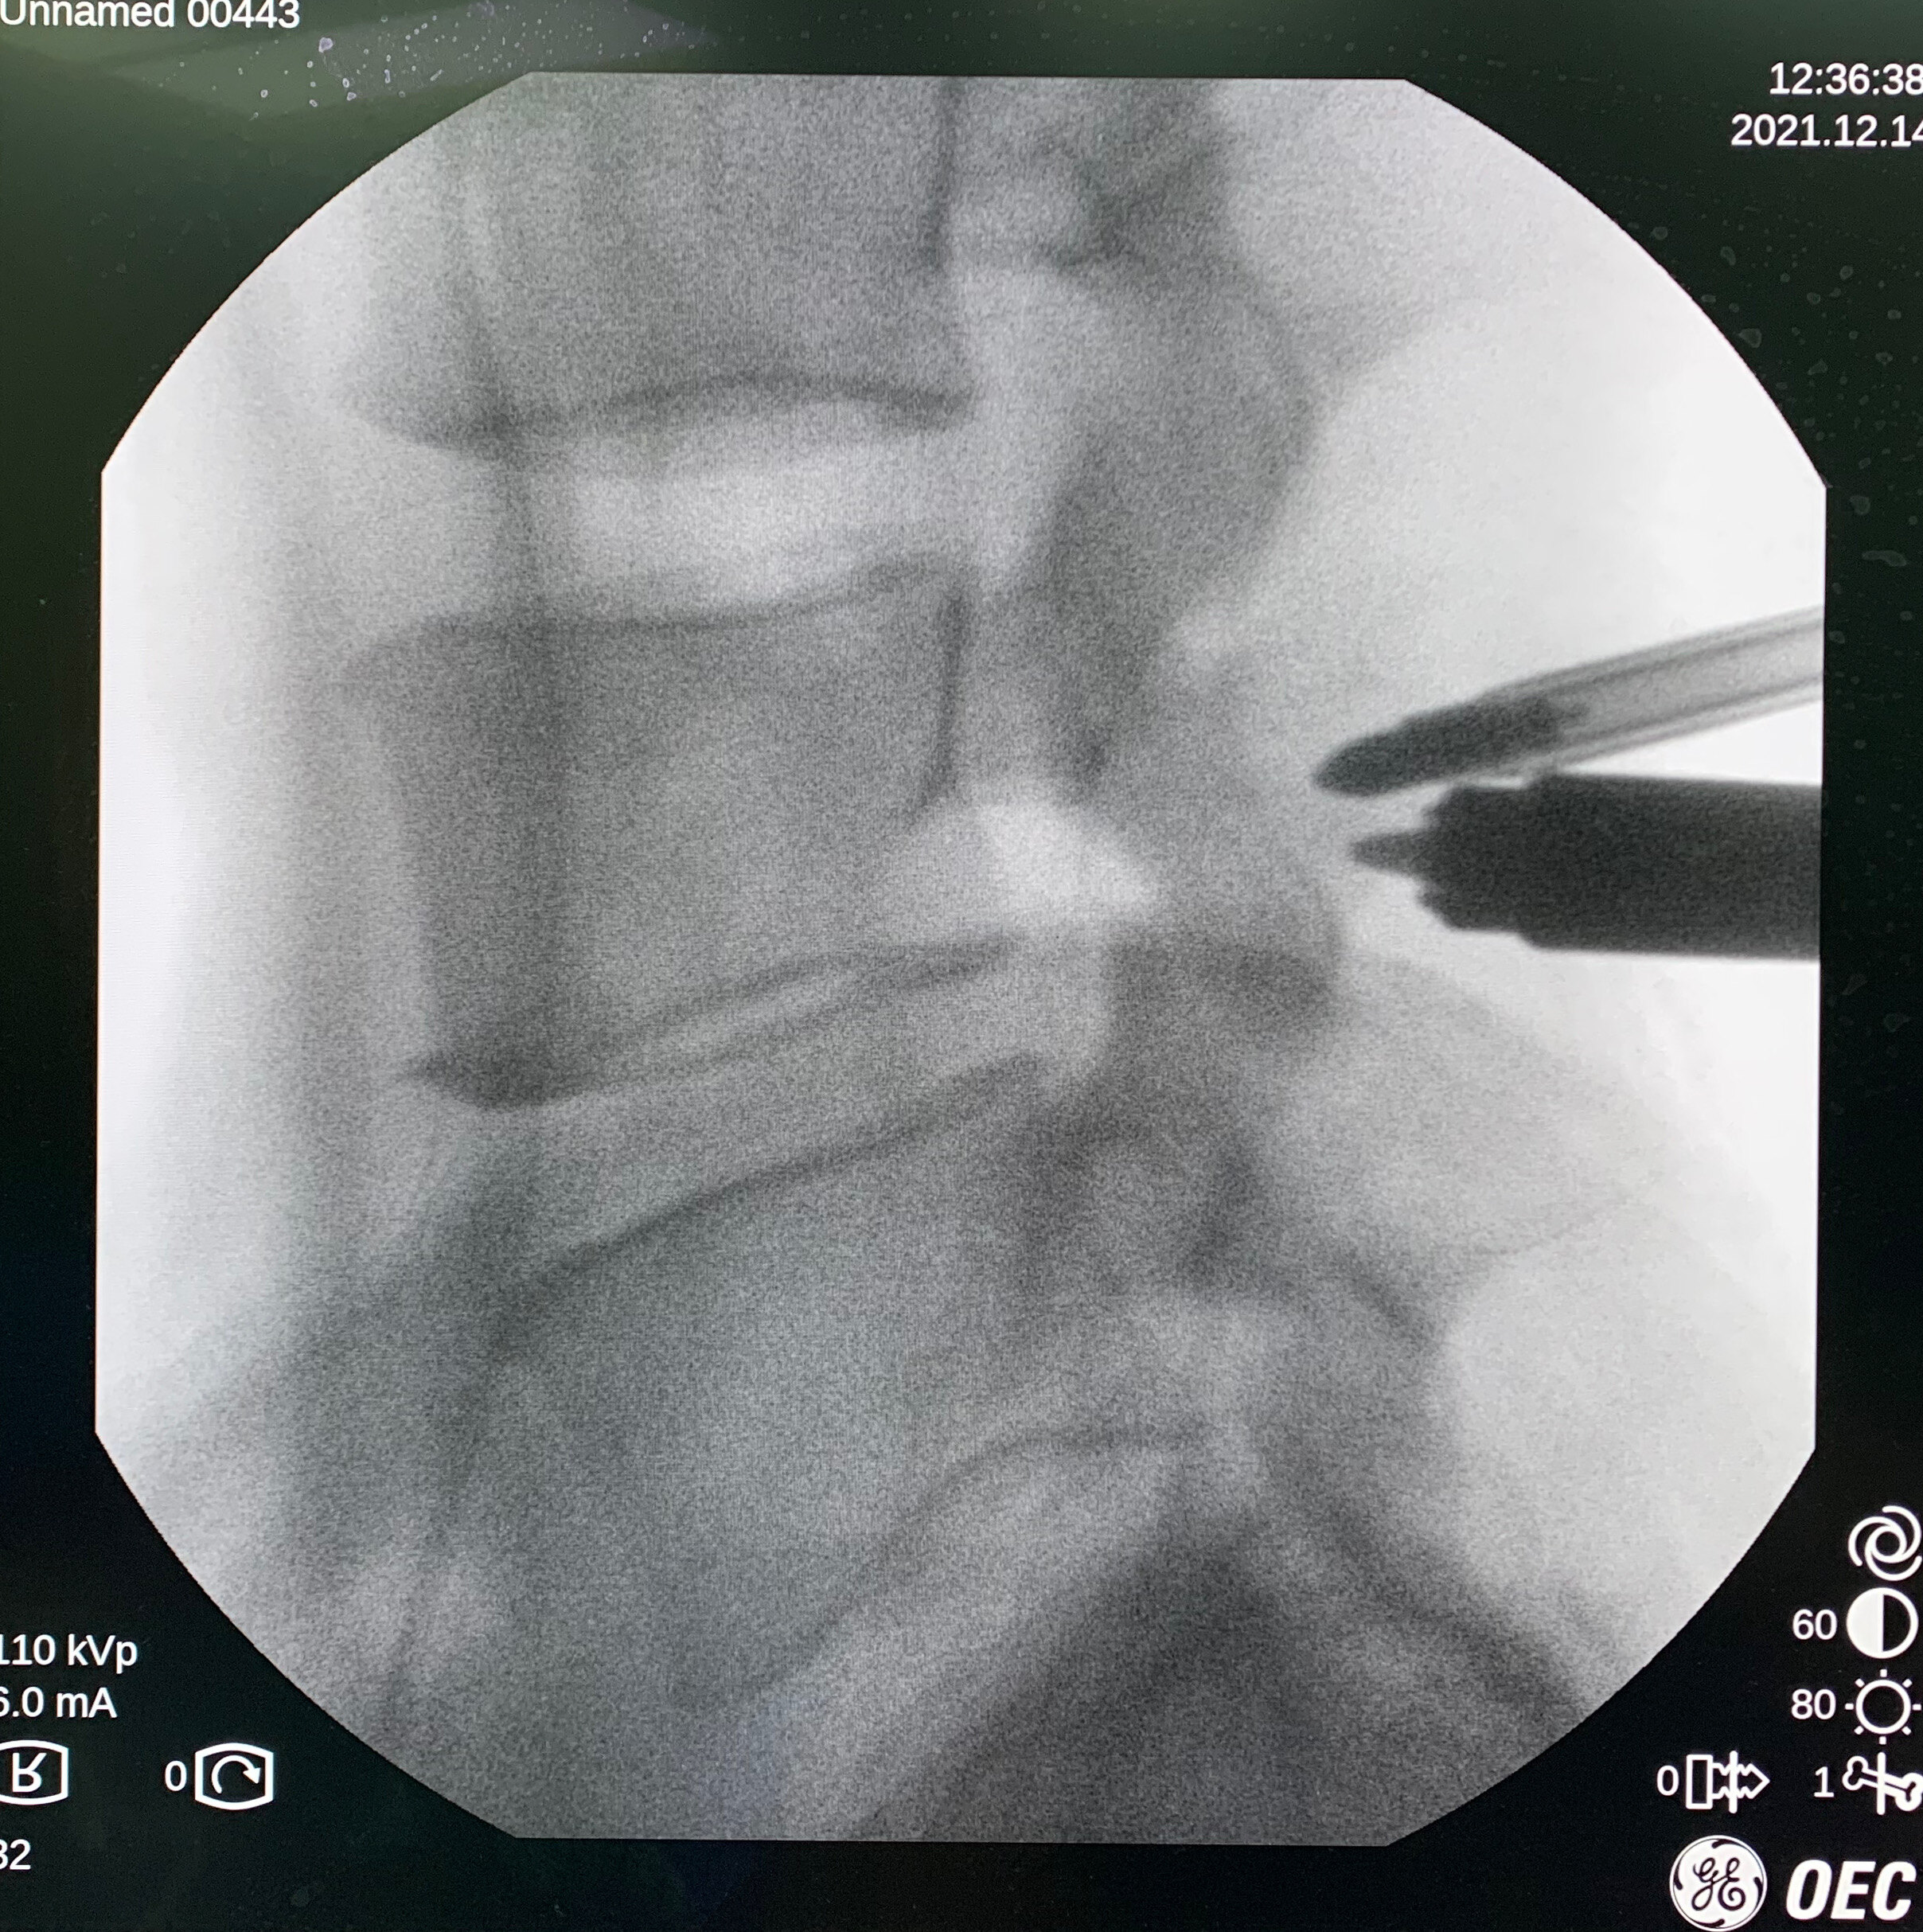

UBE技术即单侧双通道内镜技术(Unilateral Biportal Endoscopy Technique),适用于颈椎、胸椎、腰椎的退行性病变。与椎间孔镜的单通道不同,该技术通常建立两个通道,一个为观察通道,一个为器械操作通道。在UBE内镜辅助下可完成中央椎管、双侧神经根及侧隐窝狭窄的减压,并可在镜下进行椎间植骨融合的一项技术。

3.对肌肉损伤较小、透视少;